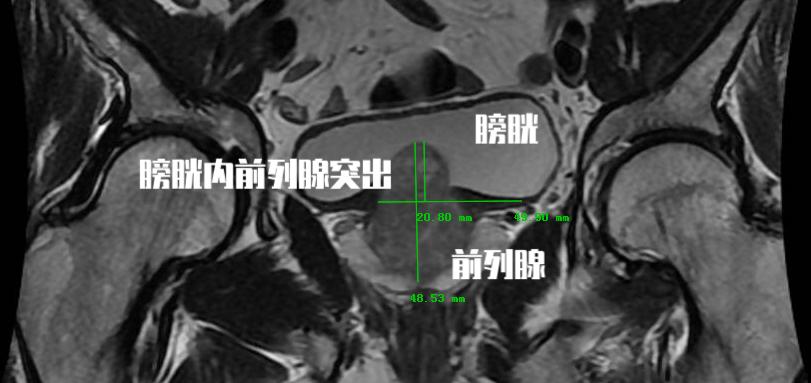

在这里首先要明确一个问题, 前列腺增生这个病本身就是前列腺体积增加 ,单论体积而言,这个病并没有什么特别的问题。 但是这个病所带来的临床症状并不单纯是前列腺增生一个问题。

可能讲起来比较难以理解, 我们男性的排尿是当膀胱内充满尿液后会有排尿的冲动信号由膀胱传递至大脑,然后大脑在可以排尿的情况下将信号在传递至膀胱和尿道。这个时候膀胱开始收缩,尿道打开,小便就可以自然排出。而前列腺增生后会带来几种情况,它会刺激我们的膀胱,即使在尿量不充盈的时候也会刺激患者要去排尿,这个时候患者表现出来的就是尿频尿急和夜尿增多,甚至出现尿*禁失**。由于尿道是从前列腺内穿行而出,增生的前列腺腺体又会对尿道产生压迫,这时候就会导致患者的排尿困难。